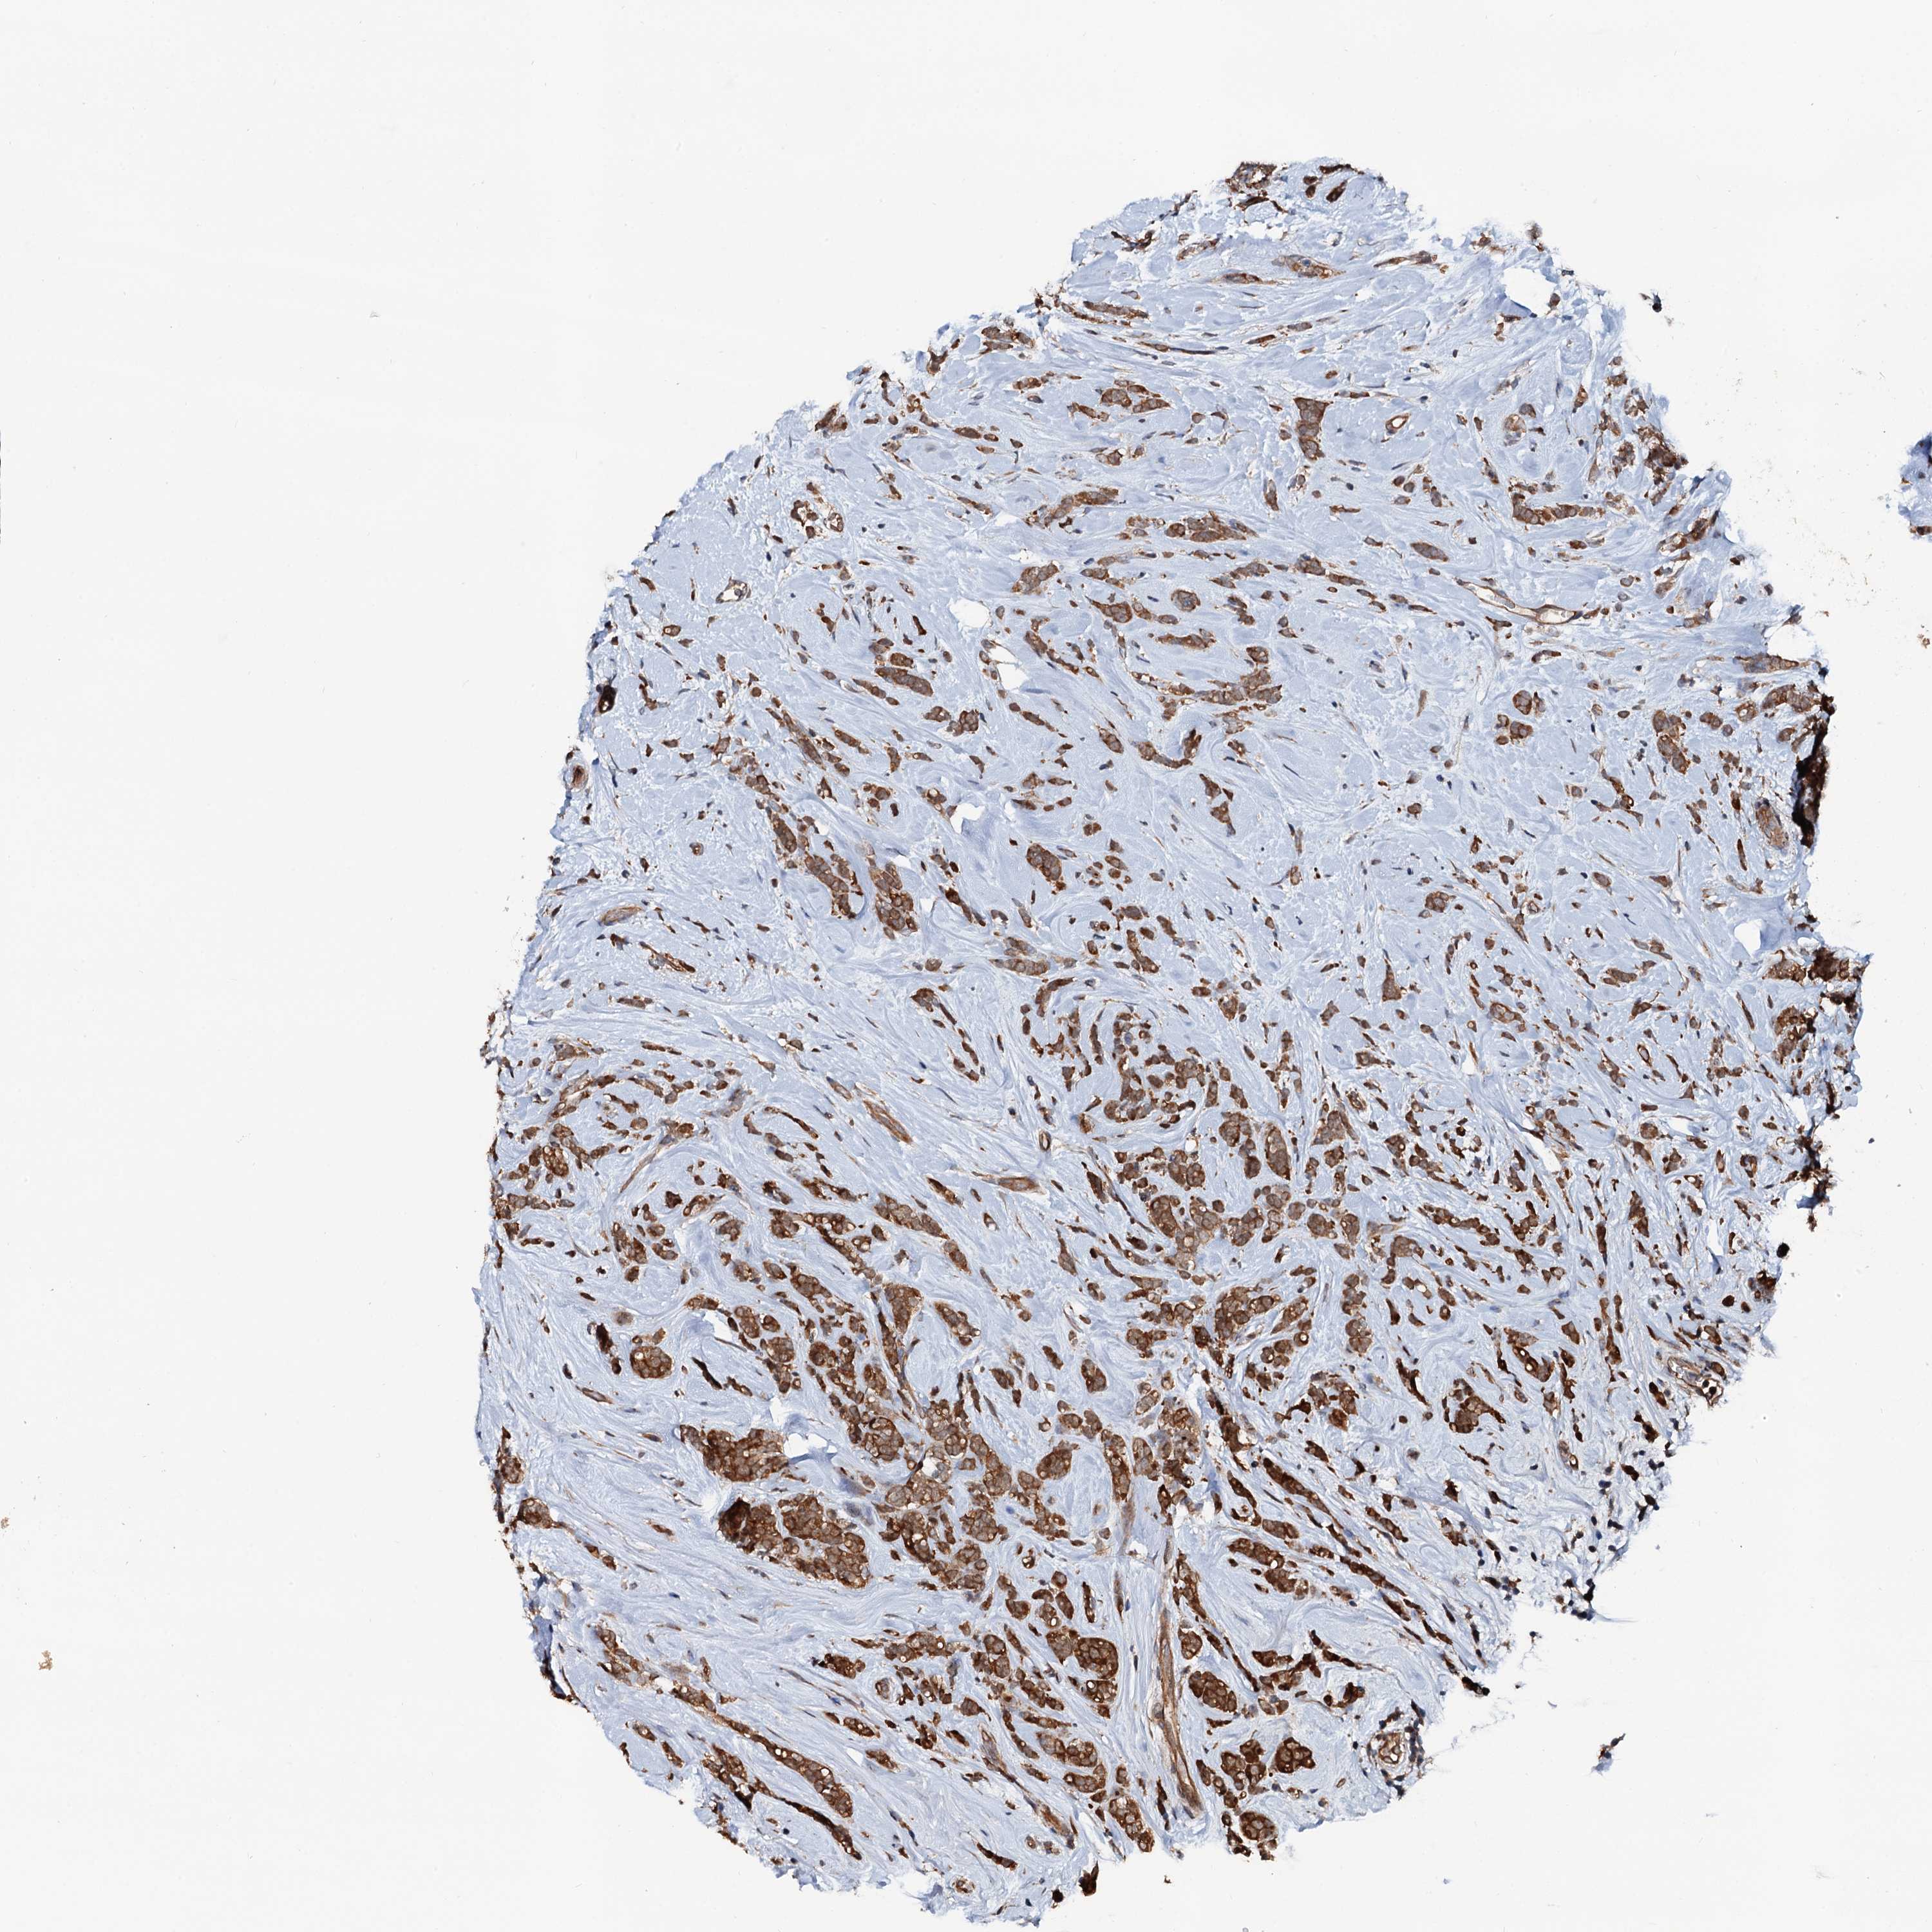

CANCER BREAST CANCER Show tissue menu

BRCA TCGA BRCA VALIDATION PROTEIN EXPRESSION